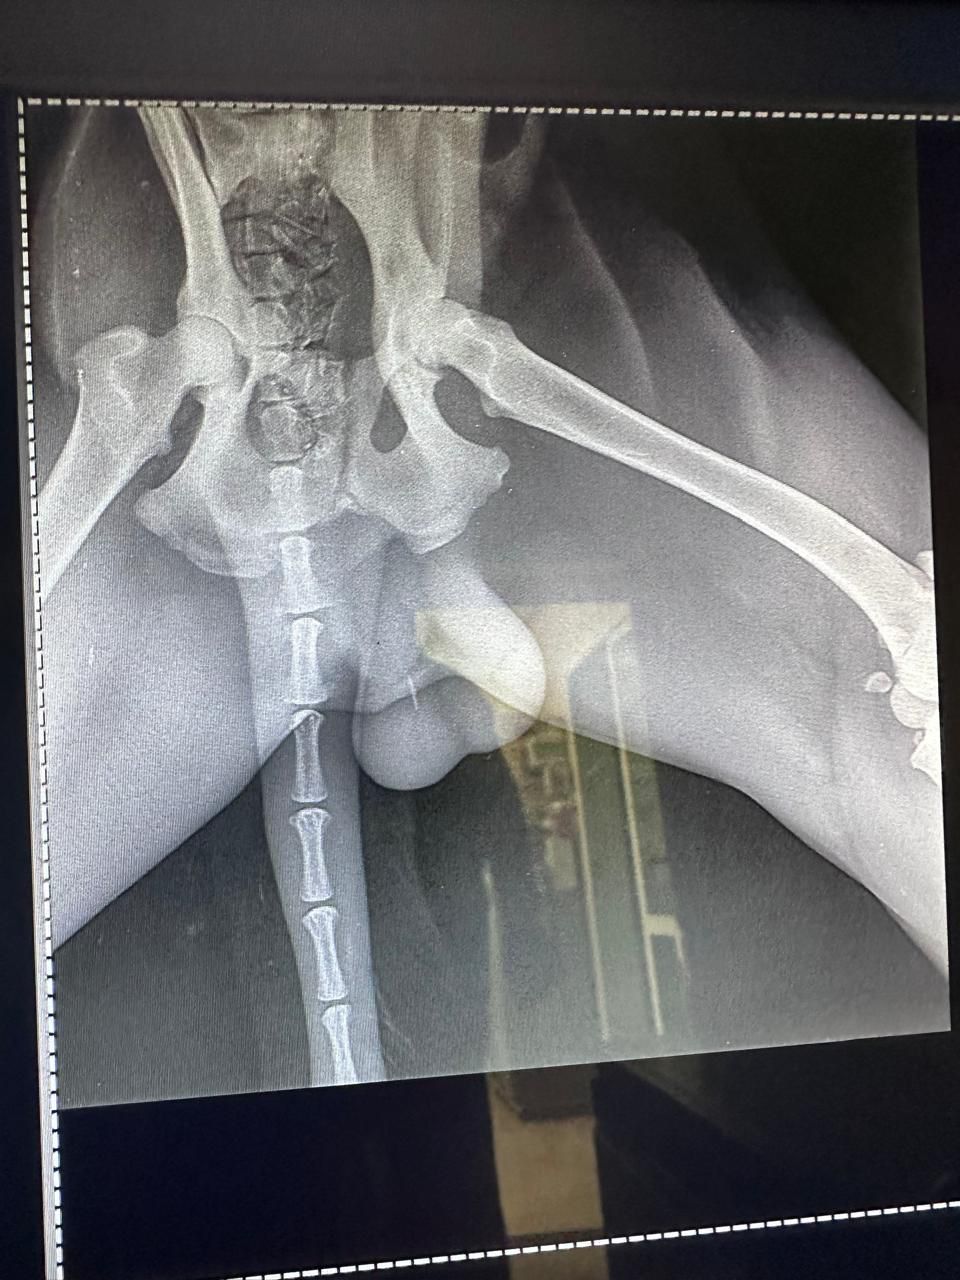

Rami trafił do naszych zaprzyjaźnionych ludzi na miejscu. Tych samych, których znacie, z którymi współpracujemy od dawna i dzięki którym setki zwierząt dostały szansę. Na jego ciele widać liczne obrażenia. Nie wiemy jeszcze, co dokładnie jest uszkodzone, bo bez diagnostyki nie da się tego ocenić. Pilnie potrzebne jest RTG, badania i dalsze leczenie. Potem kastracja, jeśli tylko jego stan na to pozwoli.